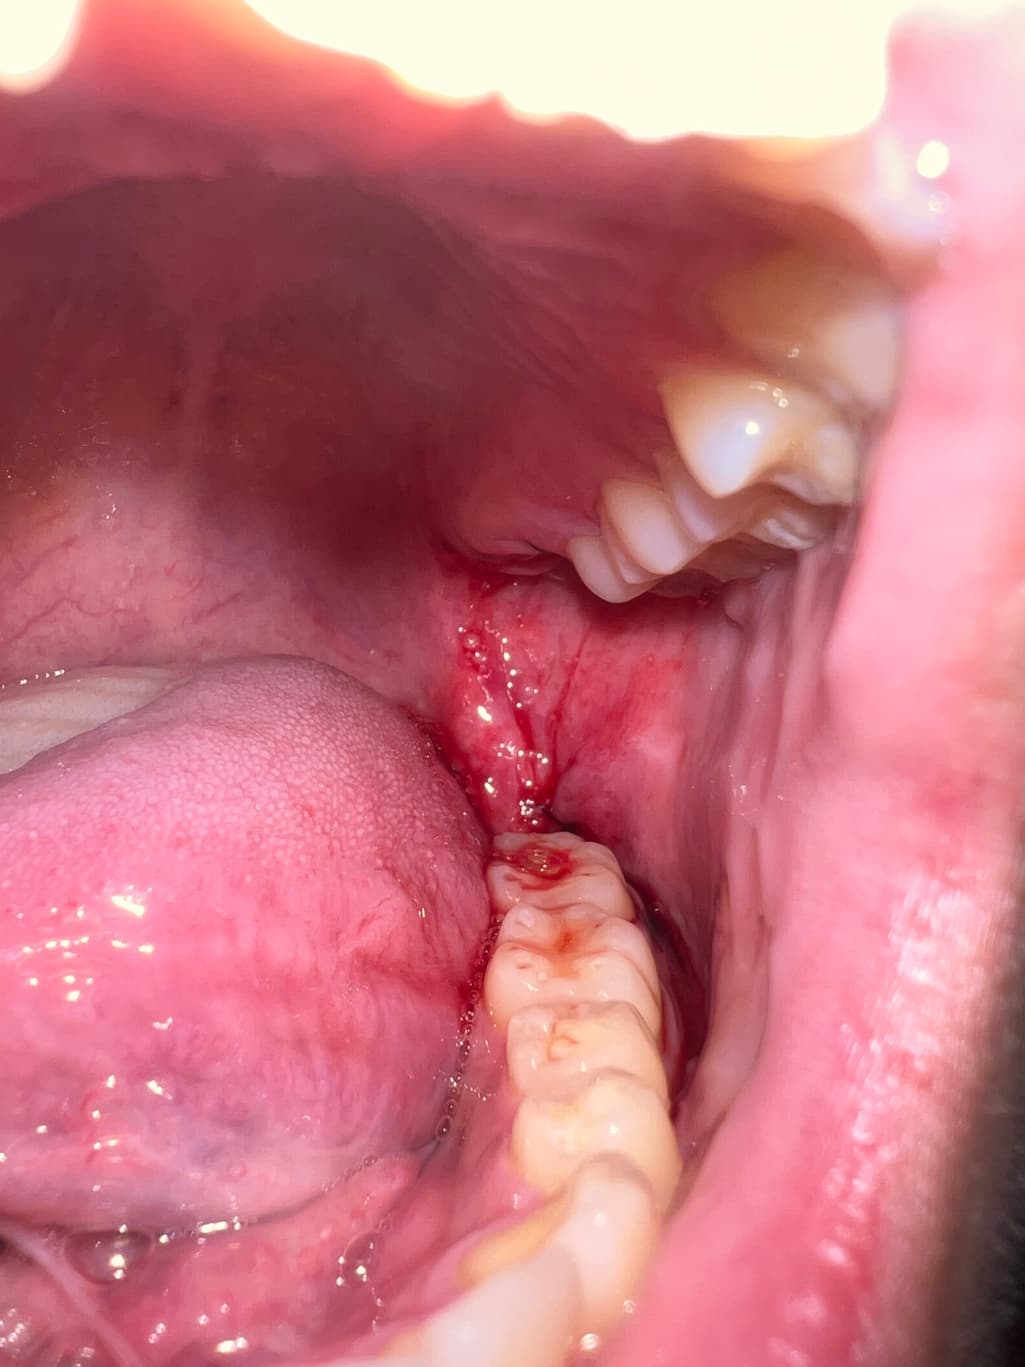

사랑니 발치했는데 이 정도면 지혈된건가요?

이번 사랑니는 지혈이 오랜시간 잘 안됐는데 이정도면 수면에는 문제 없을까요? 상악, 하악 매복 발치했고 거즈만 한 8시간 가까이 교체하면서 물었는데 뺀지는 1시간 정도 지났습니다

수면에는 문제 없을 것으로 판단되며 미세하게 피가 새어나오는 정도는 문제 되진 않습니다.

사진상으로 보면 아직 확실히 지혈이 된건 아니니 거즈를 좀더 꽉 깨물고 계시는게 좋을것같습니다.

사진으로 봤을 경우에는 지혈이 된 것으로 보입니다. 사랑니를 발치한 부위를 입을 크게 벌려 확인을 하거나 하는 행위는 발치한 부위를 자극하게 하여 출혈이 지속될 수 있습니다. 사랑니를 발치한 부위가 자극되지 않도록 하는 것이 좋습니다.